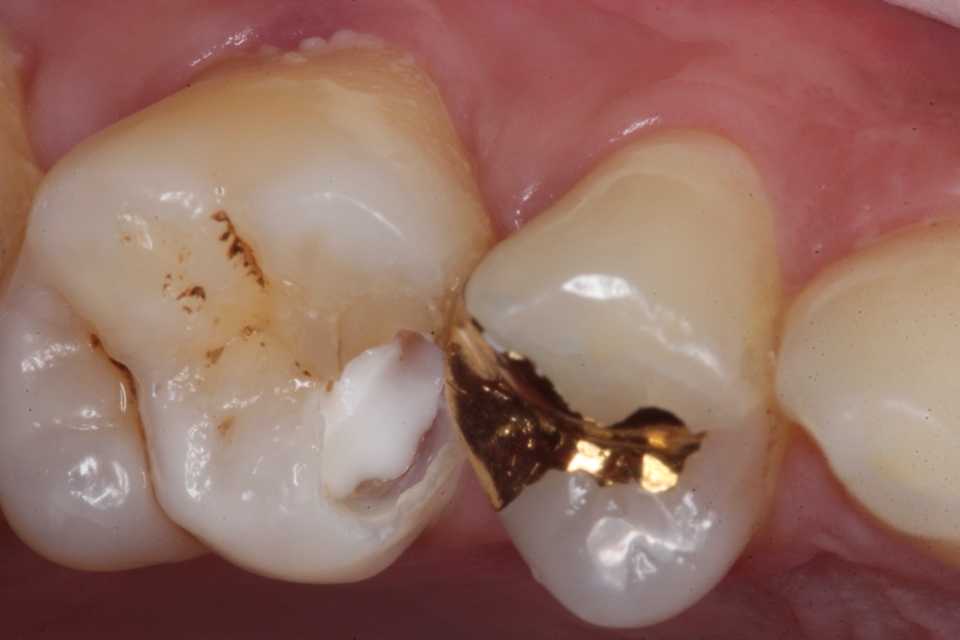

30代男性、右上6、隣接面カリエス、CR充填後(当院ではない)の2次カリエス、外傷性咬合(食いしばり)有り

今日は、10ヶ月程前に時間がないのでα-TCPで仮充填しておいた歯の治療の続き。

とりあえずα-TCPを除去し始めたが内部の象牙質は硬化している。虫歯はα-TCPで治る。

再度3MIX+α-TCPで覆罩してCR充填した。

歯肉縁下に虫歯やクラックが及んでいたができる限り取り除いた。歯肉側のエナメル質は取らざるを得なかったが、これ以上取ると大穴が開く寸前までいった。象牙質のクラックが少し見えるが、α-TCPで治って欲しい。

では時系列でどうぞ

頬側の虫歯は追求するしかない。

こういった歯肉縁下の窩洞はストリップスを使うと出血するだけで上手くいかないだろう。ましてやラバーダムなど歯肉縁下にはかからない。

難しかったので途中経過を撮る余裕がなかった。